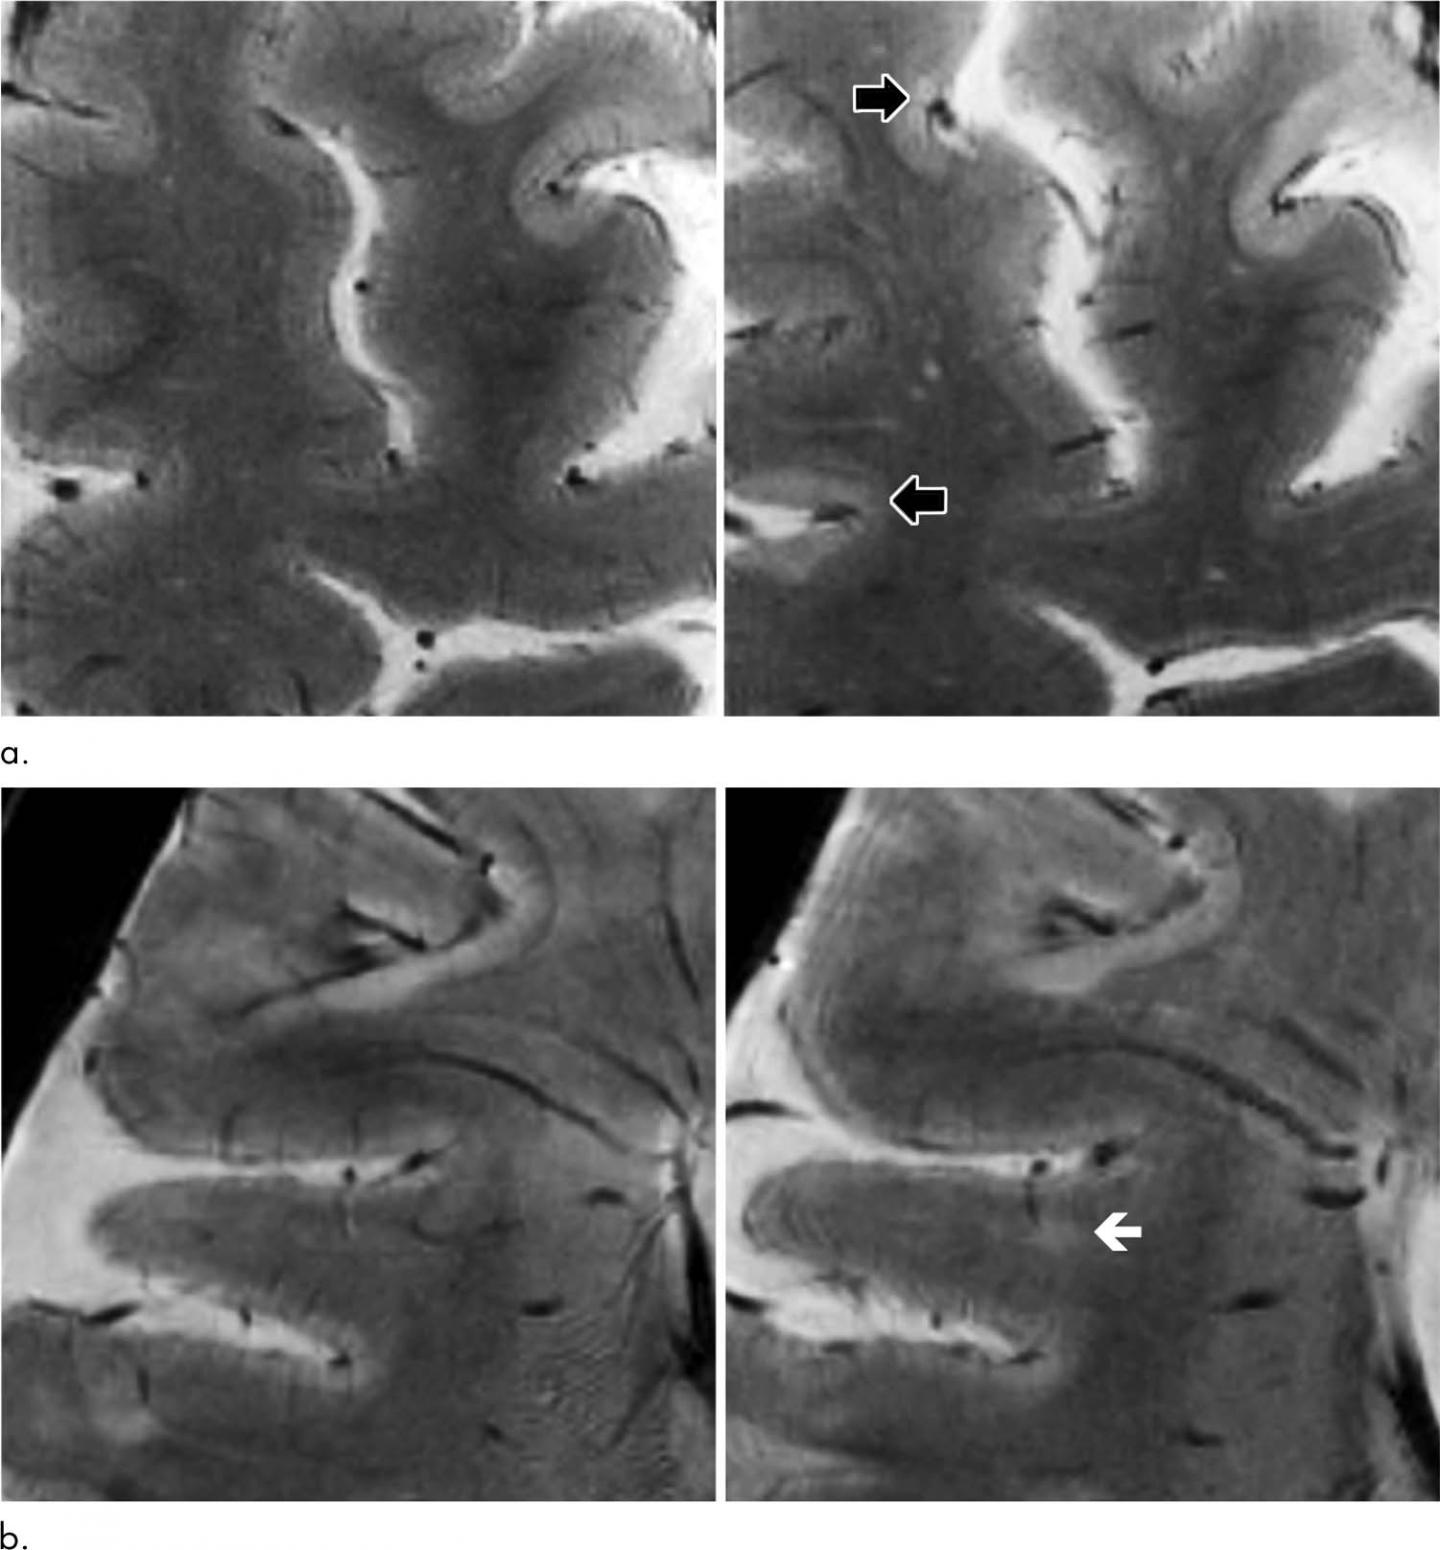

From www.ajnr.org

Reduced Diffusion in a Subset of Acute MS Lesions A Serial Ms Progression Mri Traditional mri biomarkers do not adequately track progressive ms. Mri techniques can be used as regular monitoring to help stage patients with ms and measure disease progression. In progressive ms, the mri facilitates the demonstration of the substrate of disease. Mr imaging offers clinicians a range of applications for the management of ms, including support in diagnosis, insights into pathogenesis,. Ms Progression Mri.